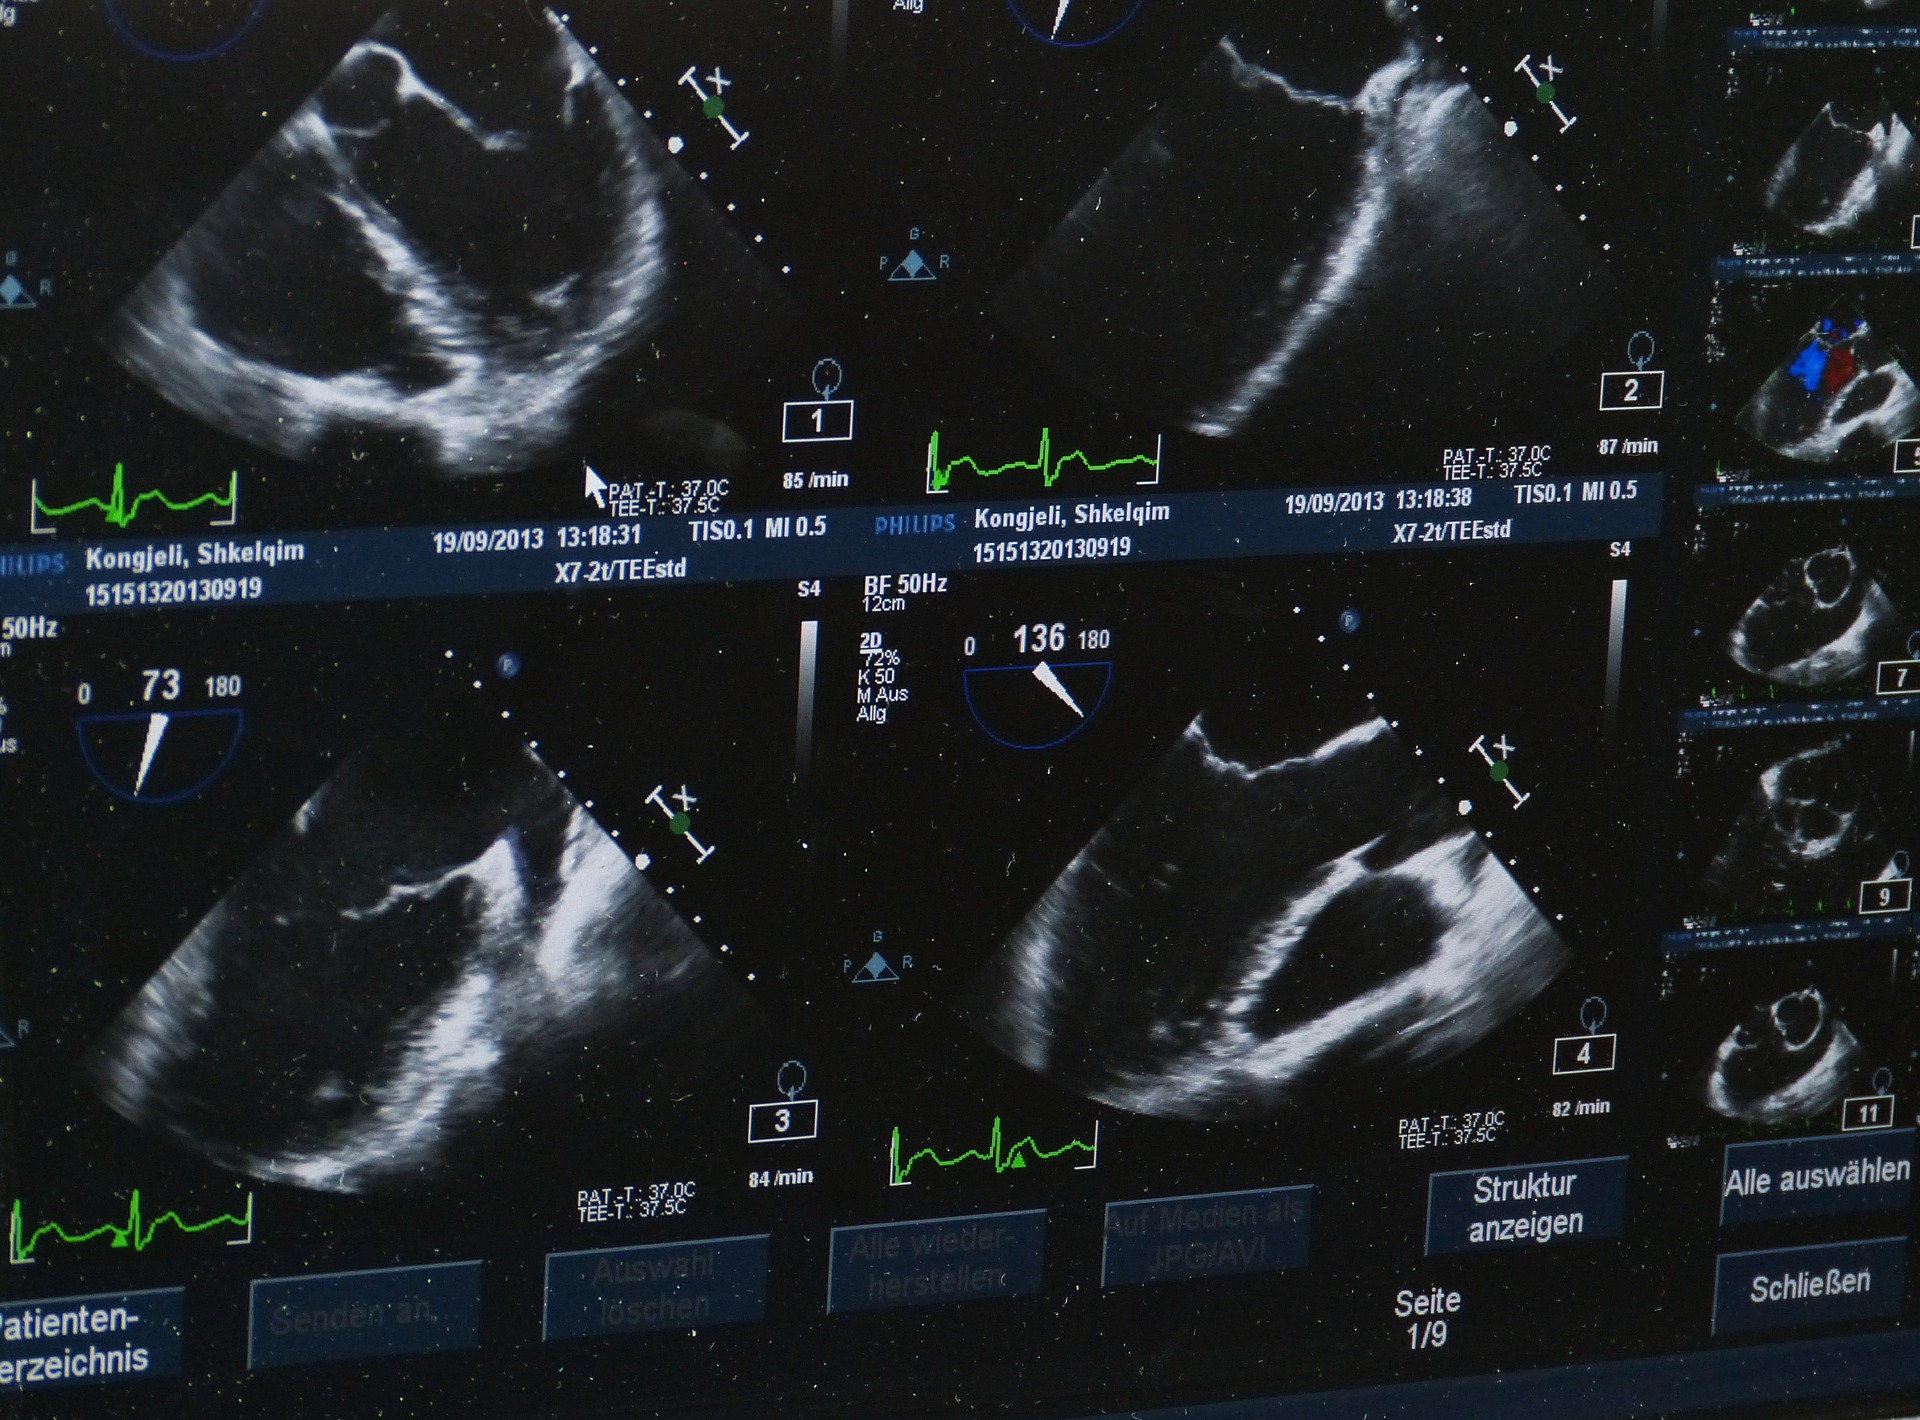

Ultrazvuk općenito koristi visokofrekventne zvučne valove kako bi se dobila slika i video organa u tijelu. Ultrazvuk abdomena potrebno je napraviti po preporuci liječnika, ako imate problema s krvnim žilama u abdomenu ili kod problema s jetrom, gušteračom, slezenom, žučnim mjehurom, bubrezima ili crijevima.

Ultrazvuk abdomena je bezbolna i kratka pretraga koja koristi zvučne valove i ne izaziva nikakvu štetu na tijelu.